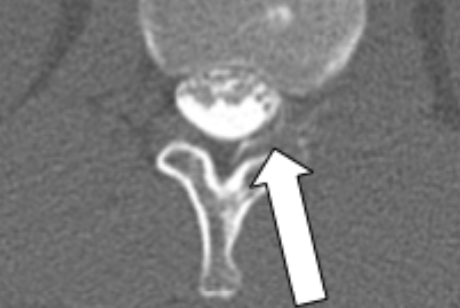

一方、画像鑑定報告書は、画像所見が争点となっているケースで用いられます。画像に写っている異常所見と後遺症の関係性を詳しく解説します。

そのため、前回の審査で画像所見が不十分とされた事案では、画像鑑定報告書が有効です。

画像鑑定報告書では、レントゲン、CT、MRIなどの各種画像検査や資料を精査したうえで、後遺障害診断書に記載されている症状との関連性を報告します。

はい、高まります。新たなMRI検査で神経根の圧迫所見や椎間板膨隆などが確認できれば、後遺障害認定基準を満たす可能性が増します。